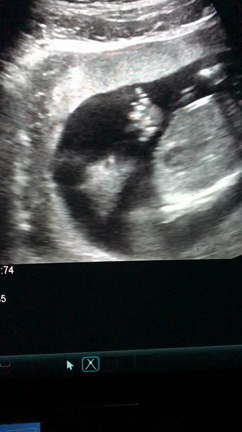

エコー動画 8w4d

2020年7月13日